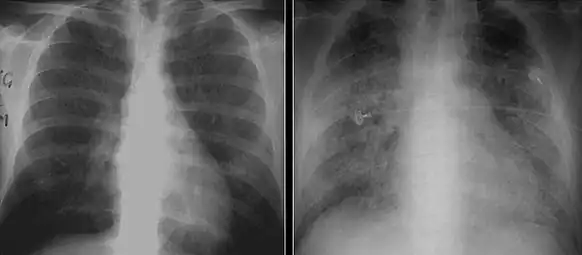

The diagnosis can be confirmed by the characteristic appearance of the chest X-ray and an arterial oxygen level (PaO2) that is strikingly lower than would be expected from symptoms. Gallium 67 scans are also useful in the diagnosis. They are abnormal in about 90% of cases and are often positive before the chest X-ray becomes abnormal. Chest X-ray typically shows widespread pulmonary infiltrates. CT scan may show pulmonary cysts (not to be confused with the cyst-forms of the pathogen).

Chest X-ray demonstrating bilateral pulmonary infiltrates caused by pneumocystis pneumonia.

Chest X-ray of increased opacification (whiteness) in the lower lungs.

These chest radiographs are of two patients. Both show ground glass opacities. The left X-ray shows a much more subtle ground-glass appearance while the right X-ray shows a much more gross ground-glass appearance mimicking pulmonary edema.[6]